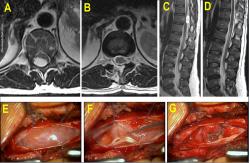

Falldarstellung: Es werden 4 Fälle mit untypischem Wachstumsverhalten und den daraus resultierenden Schwierigkeiten bei Diagnostik und Therapie gezeigt. Im Einzelnen präsentieren wir Fälle mit zystischen statt soliden Tumoren, mit retroperitonealem statt intraspinalem Wachstum, knochendestruierende statt -verdrängende Schwannome sowie Tumore mit intra- statt extramedullärer Lokalisation.